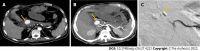

Non-variceal upper gastrointestinal bleeding (NVUGIB) is a common gastroenterological emergency associated with significant morbidity and mortality. Gastroenterologists and other involved clinicians are generally assisted by international guidelines in its management. However, NVUGIB due to peptic ulcer disease only is mainly addressed by current guidelines, with upper gastrointestinal endoscopy being recommended as the gold standard modality for both diagnosis and treatment. Conversely, the management of rare and extraordinary rare causes of NVUGIB is not covered by current guidelines. Given they are frequently life-threatening conditions, all the involved clinicians, that is emergency physicians, diagnostic and interventional radiologists, surgeons, in addition obviously to gastroenterologists, should be aware of and familiar with their management. Indeed, they typically require a prompt diagnosis and treatment, engaging a dedicated, patient-tailored, multidisciplinary team approach. The aim of our review was to extensively summarize the current evidence with regard to the management of rare and extraordinary rare causes of NVUGIB.